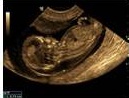

Ecografía obstétrica

La ecografía obstétrica es el método más seguro para conocer el estado general del embarazo y según las semanas de gestación tiene sus indicaciones específicas a evaluarse. Se utiliza para determinar la presencia de embarazo y conocer las condiciones del embrión o feto, así como de la placenta, el útero, cuello del útero y líquido amniótico.

El ecógrafo es un equipo con un y transductor o sonda conectado a un monitor por un cable. El transductor o sonda es un dispositivo parecido a un micrófono. El radiólogo administra un gel sobre la zona a explorar y aplicará la sonda sobre la piel. La imagen aparece inmediatamente en la pantalla. A veces la propia paciente puede ver el monitor.